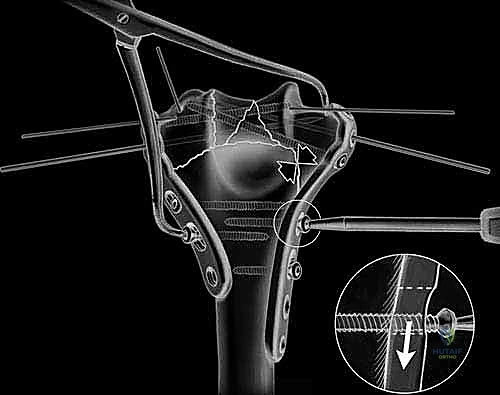

With the nerve protected, attention turns to the olecranon osteotomy. A chevron-shaped osteotomy, with the apex pointing distally, is preferred over a transverse cut as it provides inherent rotational stability and a larger surface area for healing. The osteotomy site is targeted at the bare area of the greater sigmoid notch, typically 2-3 centimeters distal to the olecranon tip. Crucially, before initiating the cut, the proximal ulna is pre-drilled and tapped for a 6.5mm or 7.3mm cannulated lag screw to ensure perfect alignment during subsequent repair. The osteotomy is initiated with a fine oscillating saw and completed with a thin osteotome to crack the subchondral bone, preserving the articular cartilage interdigitation. The olecranon fragment, with the triceps mechanism attached, is then reflected proximally, granting a breathtaking, 360-degree view of the distal humeral articular surface.

The fracture reduction sequence follows a strict "inside-out" and "bottom-up" philosophy. The primary objective is the anatomical restoration of the articular block (the "tie"). The trochlear and capitellar fragments are meticulously debrided of hematoma, reduced using pointed reduction forceps, and provisionally stabilized with smooth Kirschner wires. This articular assembly is then definitively fixed using headless compression screws or countersunk cortical lag screws, ensuring no hardware violates the joint surface. Once the articular block is reconstituted into a single, solid unit, it is reduced to the medial and lateral columns of the humeral diaphysis. Provisional fixation to the shaft is achieved with K-wires, and orthogonal fluoroscopy is utilized to confirm anatomical alignment, particularly the crucial 30-degree anterior tilt of the articular surface.

Definitive osteosynthesis is achieved through the application of dual pre-contoured anatomical plates. Following the principles of parallel plating, a plate is applied to the medial ridge and another to the lateral ridge of the distal humerus. The plates are positioned to maximize screw purchase in the distal articular block; ideally, multiple screws should interdigitate through the articular fragments, creating a "rebar" effect. The plates must be compressed to the bone using standard lag techniques or articulated tension devices before deploying locking screws. The stability of the construct is then rigorously tested by taking the elbow through a full, unhindered range of motion. Finally, the olecranon osteotomy is meticulously repaired using the previously drilled lag screw supplemented with a figure-of-eight tension band wire, or via a dedicated proximal ulna locking plate, ensuring rigid fixation to allow for immediate postoperative rehabilitation.